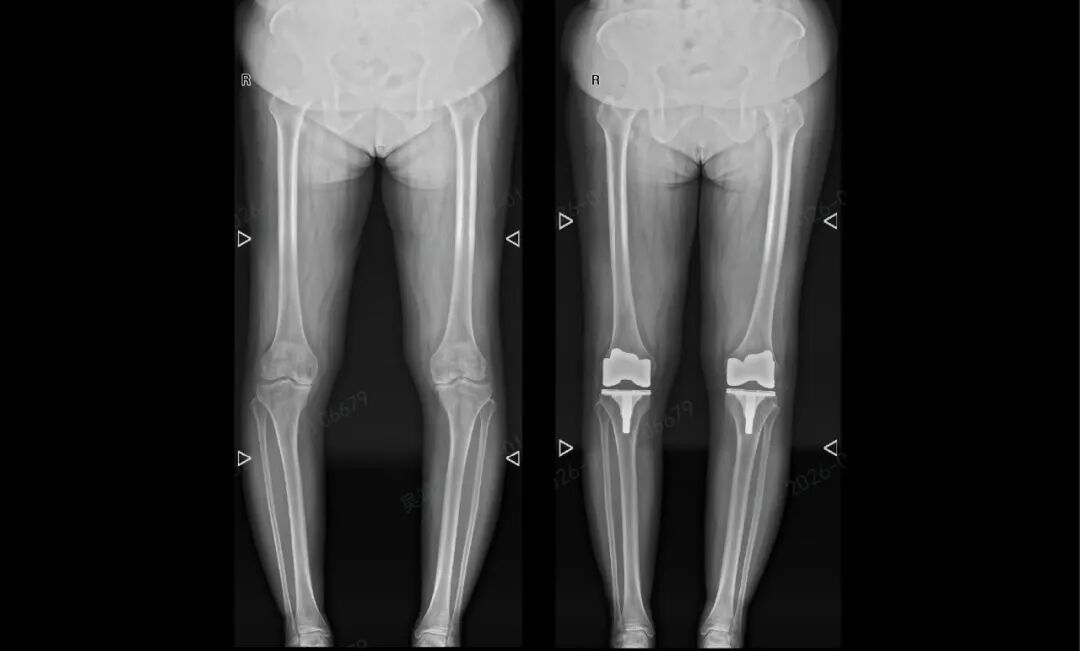

近日,北京积水潭医院郑州医院(郑州市中心医院)关节外科主任杨锴、副主任医师吴靖宇成功运用天玑机器人辅助手术系统,为一名饱受双膝重度骨关节炎困扰十年的65岁患者完成双侧全膝关节置换术,以亚毫米级精准操作突破传统手术精准度瓶颈。

可量化:从经验判断到数据决策的个体化规划。基于患者CT数据,系统构建1:1比例的3D数字膝关节模型,在天玑规划平台完成手术推演,精准测算假体安放角度、关节力线等关键参数,为患者定制专属手术方案,告别“千人一面”的诊疗模式。

可精准复制:让手术方案得以完美复制。手术过程中,机器人臂凭借稳定的操作性能,严格遵循术前规划完成骨骼切割与假体植入,操作精度控制在亚毫米级,既保障了骨骼切割的规范性,又最大程度减少对健康软组织的影响,实现微创化治疗目标。

手术结束后,患者张阿姨的膝关节畸形得到矫正,疼痛感明显改善。令人欣慰的是,她在术后次日便能自主站立,目前已顺利开展功能康复训练,逐步向正常行走目标推进。